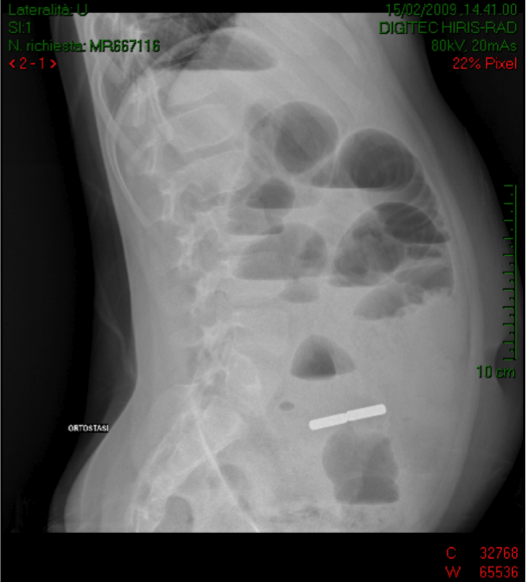

M., 11 anni, giunge alla nostra osservazione un sabato pomeriggio di febbraio per dolore addominale, vomito e alcune scariche diarroiche. La sintomatologia era comparsa qualche ora prima, all'anamnesi nulla da segnalare. All'arrivo in Pronto Soccorso � in buone condizioni cliniche generali, seppure molto addolorato; nel corso del pomeriggio ha presentato alcuni episodi di vomito e due scariche di feci semiliquide. All'esame obiettivo le mucose sono ben idratate, l'addome � teso, ma trattabile. Viene eseguito prelievo ematico che mostra leucocitosi neutrofila (GB 16.560/mmc; N 88,8%) e lieve aumento degli indici di flogosi (PCR= 2,03 mg/dl). L'ecografia addominale non rileva anomalie, l'appendice non viene visualizzata per la presenza di abbondante meteorismo intestinale. Viene quindi posizionato un accesso venoso periferico con infusione di soluzione glucosalina e il bimbo viene ricoverato in osservazione breve e posto in terapia antibiotica con ampicillina+sulbactam. Durante la notte presenta altri 3 episodi di vomito, poi riposa tranquillo. Nella mattinata successiva si ha un peggioramento del quadro clinico addominale con persistenza del vomito, divenuto biliare, addome globoso, teso, difficilmente trattabile. Il chirurgo, chiamato in consulenza nel sospetto di appendicopatia, consiglia posizionamento di sonda rettale per detendere l'addome, e ripetizione degli esami ematici, che risultano invariati rispetto alla sera precedente. M. viene mantenuto a digiuno e, per il peggioramento del quadro addominale e la persistenza di vomito, viene ripetuta eco addome che mostra marcata distensione delle anse del tenue, con presenza di quota fluida endoperitonaeale, ed Rx diretta addome che mostra un quadro di occlusione intestinale con livelli idroaerei e, in fossa iliaca destra, la presenza di un'immagine �a bastoncello�, duplice, della lunghezza totale di 5 cm, a densit� metallica (Figura 1). Al bambino e ai genitori viene quindi ripetuta l'anamnesi, con domande accurate sull'eventuale ingestione di corpi estranei nei giorni immediatamente precedenti la sintomatologia. Ma M. nega! Nel frattempo viene comunque attivata la sala operatoria per un intervento in urgenza.

Figura 1 All'apertura del peritoneo si assiste alla fuoriuscita di abbondante materiale corpuscolato. Le anse ileali sono ectasiche ed edematose, con presenza di due piccole aree di perforazione, in corrispondenza dei due corpi estranei. Attraverso il lume appendicolare viene poi estratto un corpo estraneo cilindrico, magnetico, che attira lo strumento chirurgico. Viene inoltre resecata una tenace briglia occludente, verosimilmente congenita, a valle delle anse ectasiche. L'Rx addome di controllo mostra poi la presenza di un altro corpo estraneo metallico, analogo a quello rimosso in sala operatoria, proiettantesi sul sacro, che viene poi espulso spontaneamente in 10� giornata post-operatoria (Figura 2).